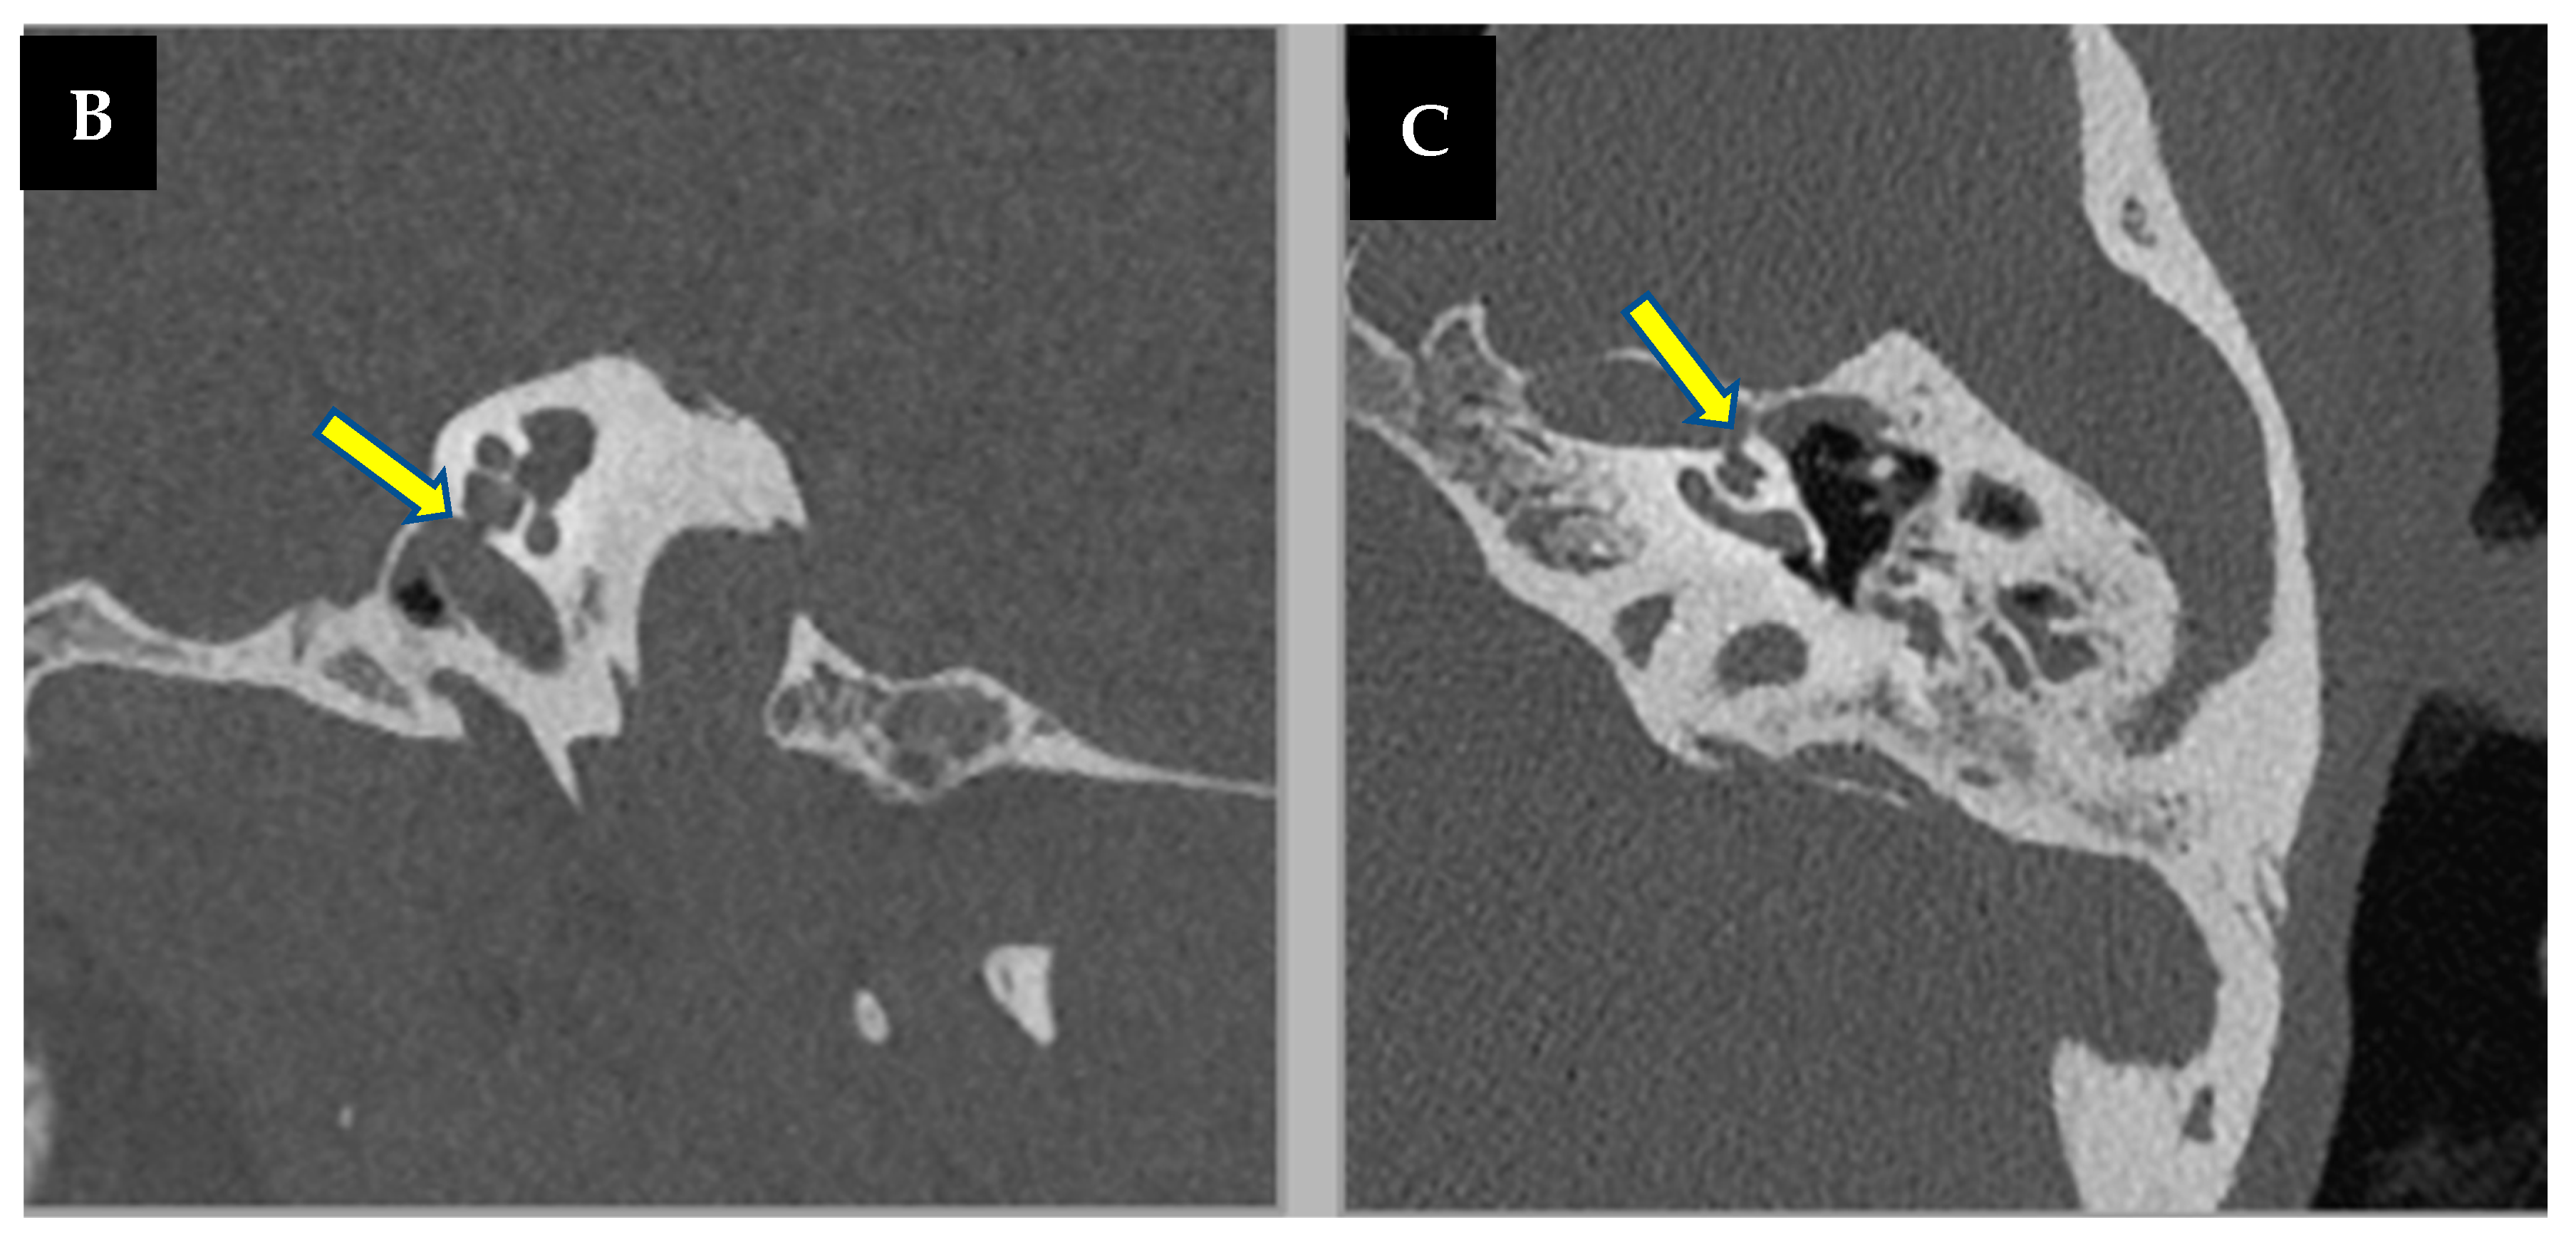

3.1. Case 1

3.2. Case 2

3.3. Case 3

3.4. Case 4

3.5. Case 5

3.6. Case 6